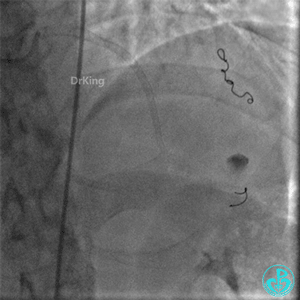

撤回逆向导丝及微导管造影,钝缘支远端侧支造影剂渗漏,局部造影剂滞留范围不断扩大。

前降支末梢经微导管释放3.0×2.5mm弹簧圈封堵破口。

钝缘支经微导管释放5.0×5.5mm弹簧圈封堵破口。